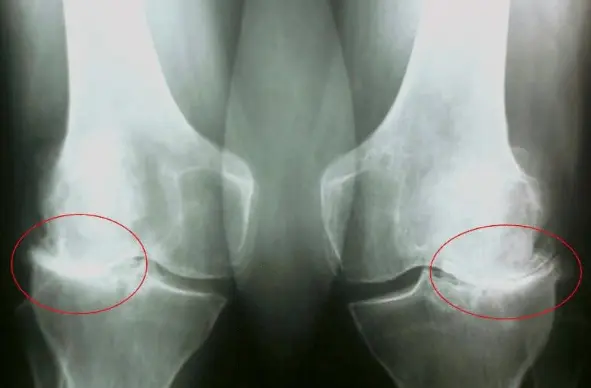

Шикастланган бўғимлар нима? Бу занг билан тўлган механизмларга ўхшайди. Натижада нима содир бўлади? Натижада ҳаракатланиш оғирлашади ва оғриқ пайдо бўлади. Бўғимлар билан ҳам худди шундай ҳодиса рўй беради. Уларда тузлар ёки бошқа моддалар тўпланганда, шиш пайдо бўлади ва оғриқ кучаяди. Натижада, барча органлар ва тизимлар азият чекади, чунки ҳаракат чекланади.

Бўғимлар аста-секин шундай емирилади. Агар сиз уларни ҳеч қачон

тикламаган бўлсангиз ва 40 ёшдан ошган бўлсангиз, у ҳолда сизнинг бўғимларингиз

жуда шикастланган. Агар сиз буни ҳали сезмаган бўлсангиз,

тез орада бу сизнинг соғлиғингизга таъсир қилади.